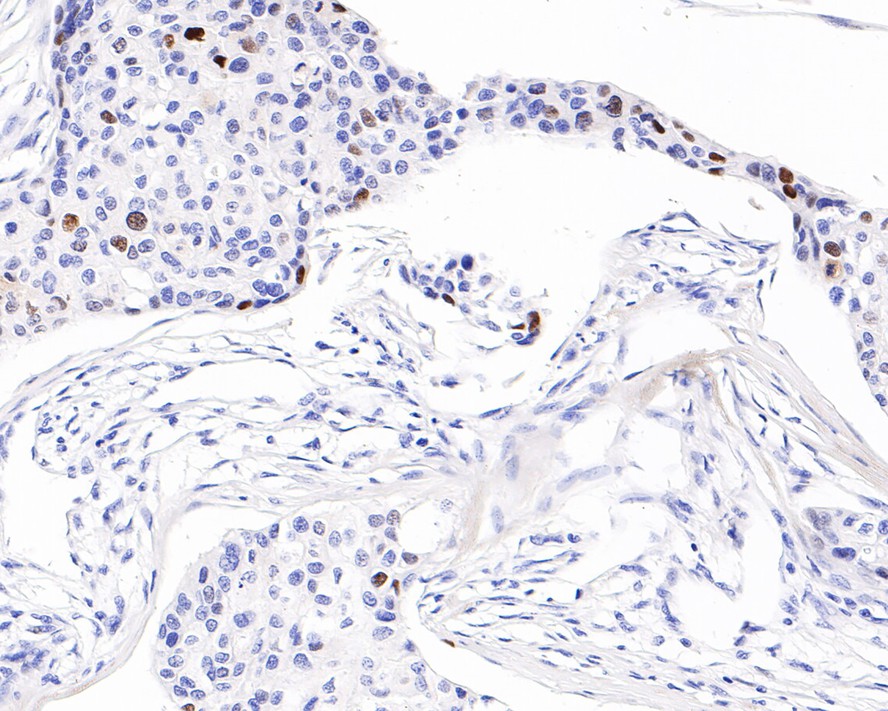

Catalog# HA601018

p21 Mouse Monoclonal Antibody [A8C11]

IHC-P

Human